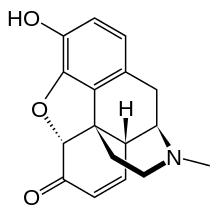

Several semi-synthetic opioids were developed in Germany in the 1910s. The first, oxymorphone, was synthesized from thebaine, an opioid alkaloid in opium poppies, in 1914.[228] Next, Martin Freund and Edmund Speyer developed oxycodone, also from thebaine, at the University of Frankfurt in 1916.[229] In 1920, hydrocodone was prepared by Carl Mannich and Helene Löwenheim, deriving it from codeine. In 1924, hydromorphone was synthesized by adding hydrogen to morphine. Etorphine was synthesized in 1960, from the oripavine in opium poppy straw. Buprenorphine was discovered in 1972.[228]

Opium alkaloids and derivatives

Phenanthrenes naturally occurring in (opium):